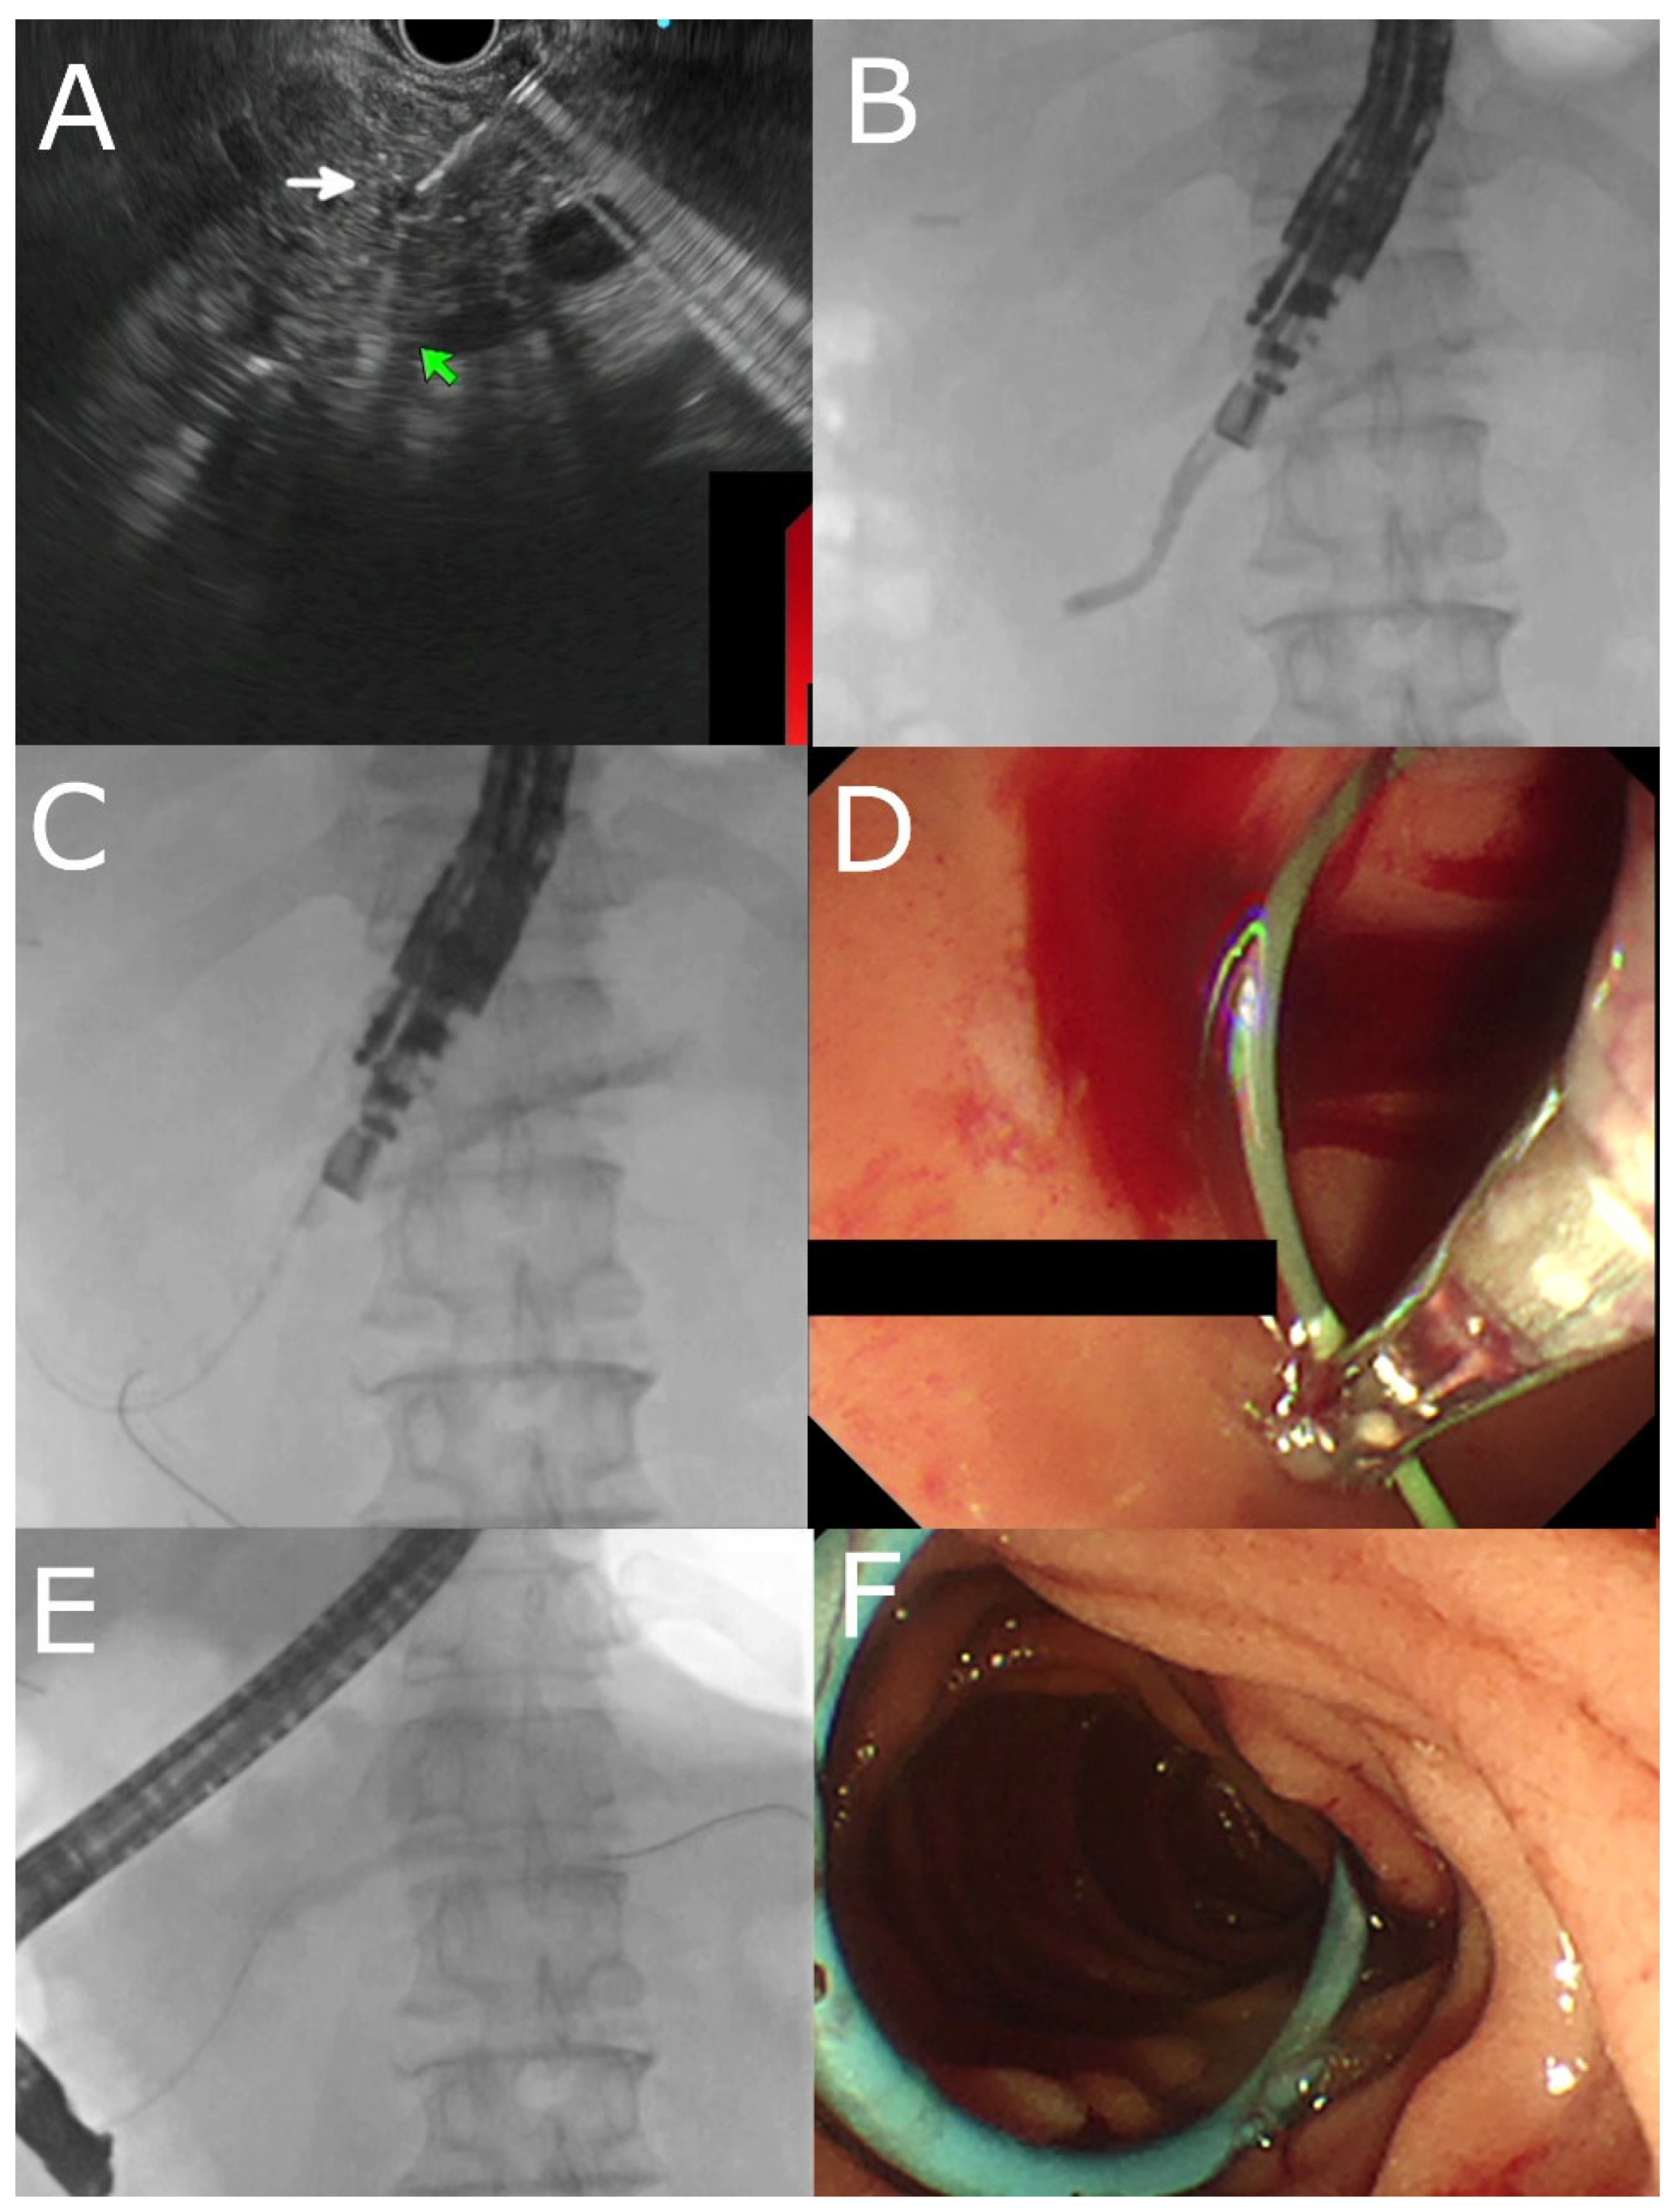

4.4. EUS- RV ERP

4.5. Transmural Approaches with Transpapillary or Trans-Anastomotic Stenting

4.6. Transmural Stenting with Antegrade/Retrograde Stenting